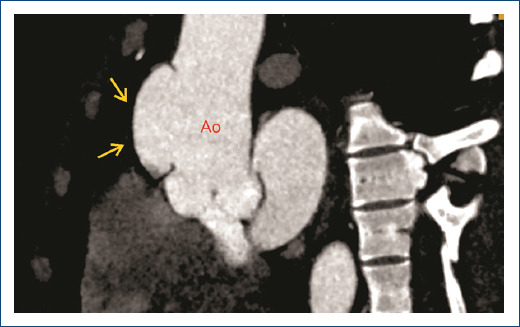

一名慢性肾病患者无症状的斯坦福A型主动脉夹层。

Asymptomatic stanford A aortic dissection in a patient with chronic kidney disease.